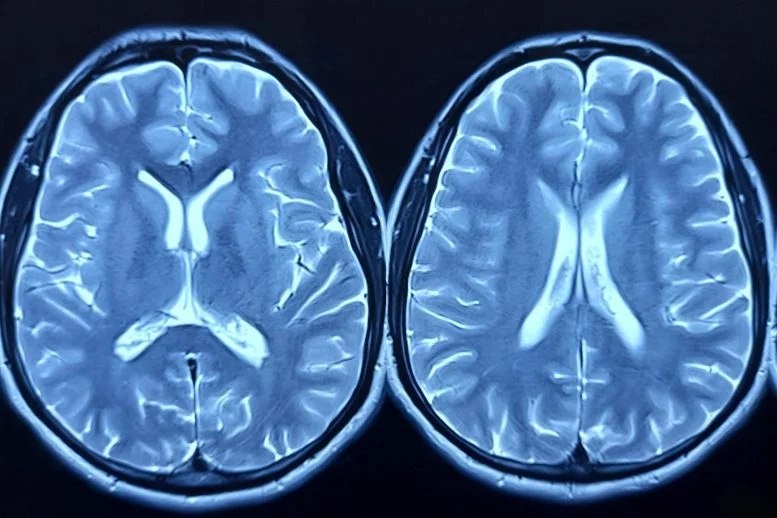

🧠✨Новое исследование показывает, что препараты для похудения, влияющие на "центр вознаграждения" в мозге, могут лишь временно снижать тягу к еде. Ученые наблюдали за мозговой активностью пациентки с ожирением, принимавшей тирзепатид (препарат, используемый при диабете 2 типа). Сначала препарат снизил активность в области мозга, отвечающей за "пищевой шум" - навязчивые мысли о еде. Однако, спустя несколько месяцев, этот эффект ослаб, и тяга к еде вернулась. Это поднимает важный вопрос: могут ли эти препараты быть долгосрочным решением для борьбы с расстройствами пищевого поведения или нужны более целенаправленные подходы? Необходимы дальнейшие исследования, чтобы понять, как эти препараты влияют на мозг в долгосрочной перспективе. #наука #медицина #мозг #питание